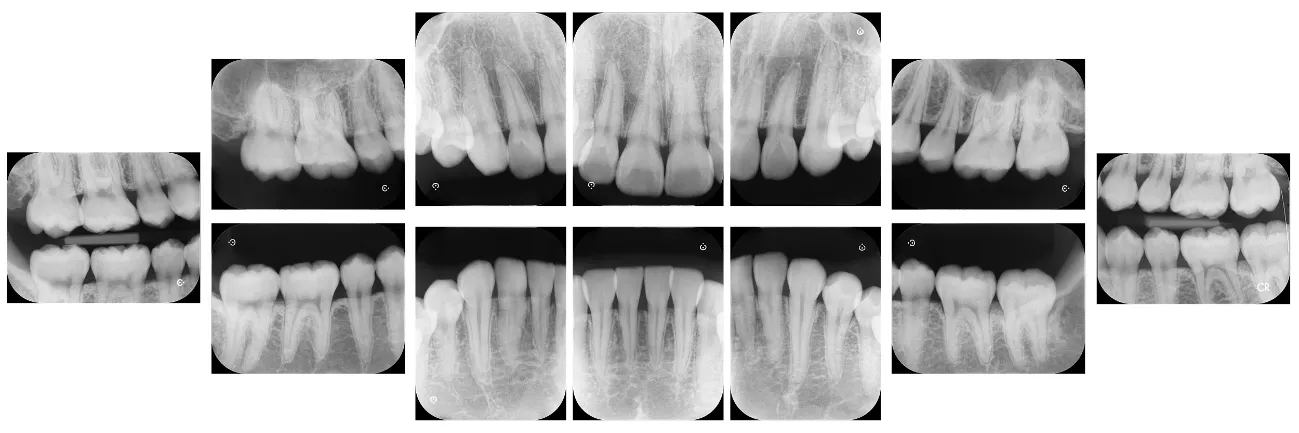

- 細かいブロックのレントゲン写真

- 肉眼では分からない歯と歯の間のむし歯や神経をとった歯の状態など細かくチェックします。